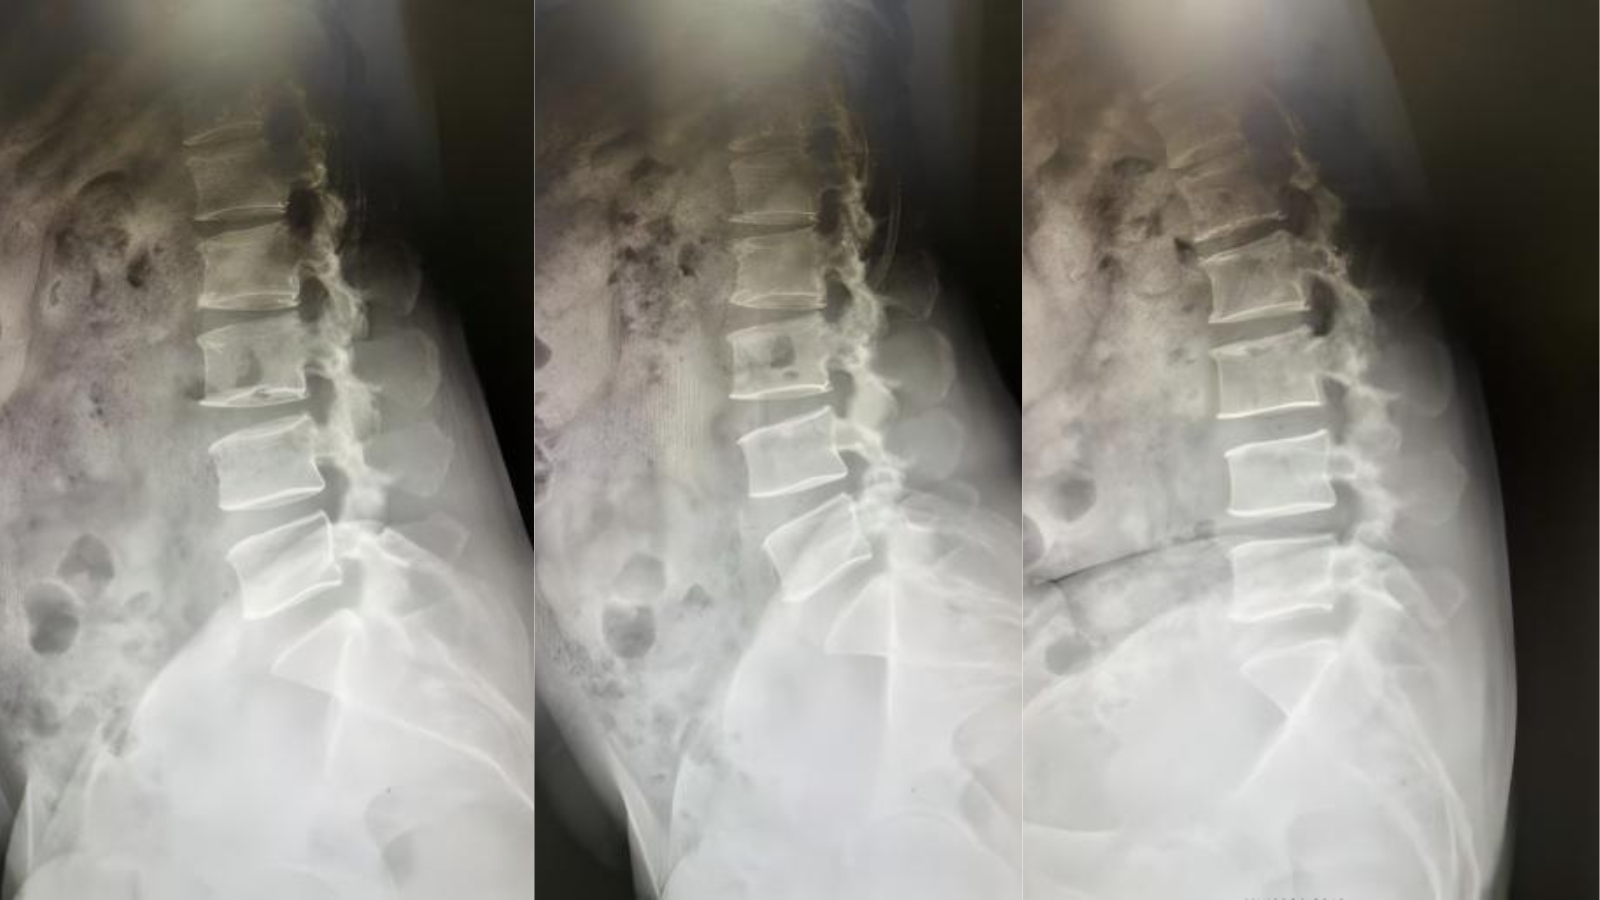

51岁的张大姐被腰腿疼痛折磨了好长一段时间,试了各种保守治疗都不见好转。片子显示腰4-5椎管狭窄、腰4退变性后滑脱症、腰4-5退变性不稳症等,要做传统开刀手术的话,伤口大、恢复慢,让她纠结了好久~